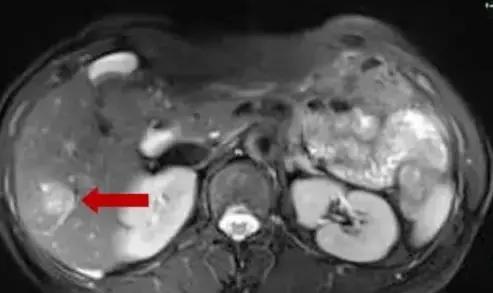

患者,女性,61岁,因反复右下腹疼痛3月,阵发性,可自行缓解,无呕吐,无发热,无胸闷、心悸,大便每日一次,无便血,无血尿,今我院肠镜检查提示:升结肠占位。门诊以“升结肠肿瘤”收治入院进一步诊治。入院后实验室检查:CEA:23.23ng/ml,行CE-MR和PET-CT均提示伴肝右叶后下段转移,大小约2cm。

肝右后叶转移灶

术前MDT讨论,拟行超声引导下肝转移瘤射频消融术+腹腔镜下右半结肠癌根治术。在超声引导下肝转移射频消融术前讨论,考虑肝内转移病灶临近肝包膜下,病灶边缘可见肝右静脉及其分支环绕,拟行双针多点重叠消融,术中遵循消融范围至少≥癌周1cm,先深后浅原则,先沿肝静脉布针,两针间距不超过2cm。